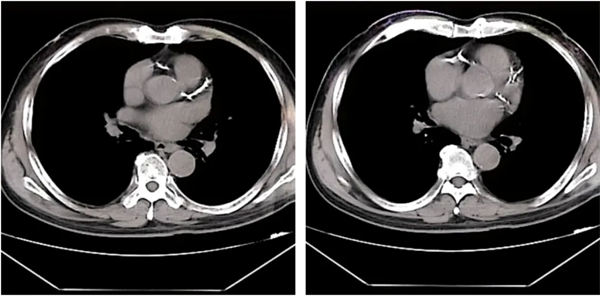

73歲的孟老先生,近期總感覺胸悶氣短,這癥狀斷斷續(xù)續(xù)三年了,近一周來癥狀加重,就診于我院心血管內(nèi)二科,患者既往有“持續(xù)性心房顫動(dòng)、高血壓”病史。入院后完善胸部CT提示:冠脈走形區(qū)鈣化明顯。

鄭廣生與患者及家屬充分溝通病情后建議行冠脈造影檢查,考慮患者冠脈鈣化嚴(yán)重,普通介入治療存在難度,術(shù)中需采用旋磨治療充分預(yù)處理病變后,再行球囊擴(kuò)張及支架植入治療。